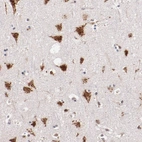

Immunohistochemical staining of human cerebral cortex shows strong cytoplasmic positivity in neuronal cells.